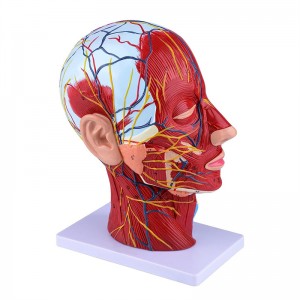

| פֿעיִקייטן | דער מאָדעל ווייזט די היגע מאָרפאַלאַדזשי פון די ינער און ויסווייניקסט זייטן פון די מידיאַן סאַגיטטאַל אָפּטיילונג פון די קאָפּ און האַלדז, און די סטראַקטשערז פון בלוט כלים און נערוועס און עס זענען 84 פּאַרץ ינדאַקייטינג וואונדער אין גאַנץ. |

【Superficial Neurovascular Muscle Model】Highly detailed, numbers marked, detachable ear, deepen the understanding of the superficial muscles, vessels, nerves and the internal structures of the head & neck. רויט-אַרטעריע, בלוי-אָדער, געל-נערוו.

【פֿעיִקייטן】 עס געוויזן די אויבנאויפיקער מאַסאַלז פון די יקספּאָוזד פּנים; די אויבנאויפיקער בלוט כלים & נערוועס פון די פּנים & סקאַלפּ; די ינער סטראַקטשערז פון פּאַראָטיד דריז & אויבערשטער רעספּעראַטאָרי שעטעך; די סאַגיטטאַל קרייַז-אָפּטיילונג סטרוקטור פון די סערוואַקאַל רוקנביין.

דער מאָדעל געוויזן די היגע מאָרפאַלאַדזשי פון די מעדיאַל און לאַטעראַל סאַגיטטאַל סעקשאַנז פון די קאָפּ און האַלדז און די וואַסקיאַלער און נערוו סטראַקטשערז, מיט אַ גאַנץ פון 100 פּלאַץ ינדאַקייטערז.